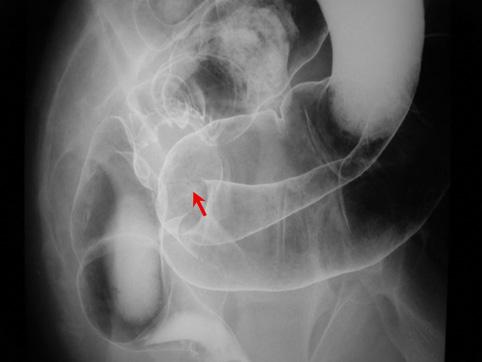

질환(병리주체)의 분류 종양양 병변/자궁내막증

부위(장기별) 대장/직장

검사방법 X-P

종양의 최대경(밀리미터) 40이상